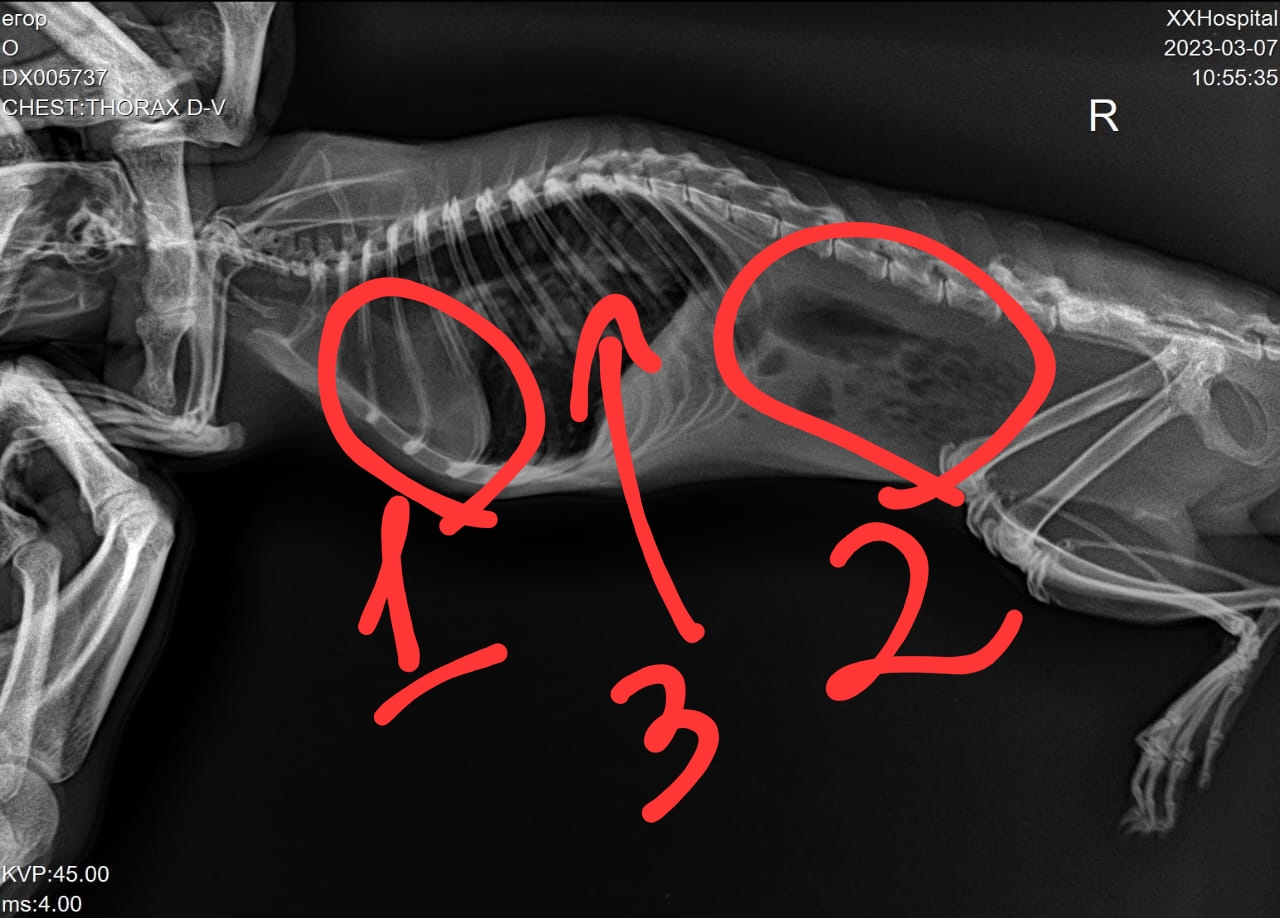

Вообще, если получится сделать ей рентген в обычной ветклинике(голову в прямой и боковой проекции), то пришли сюда снимки - там они в клинике не разберутся, но я гляну. Если сам не пойму, попытаюсь связаться со своей клиникой - вдруг там что-то сидит.